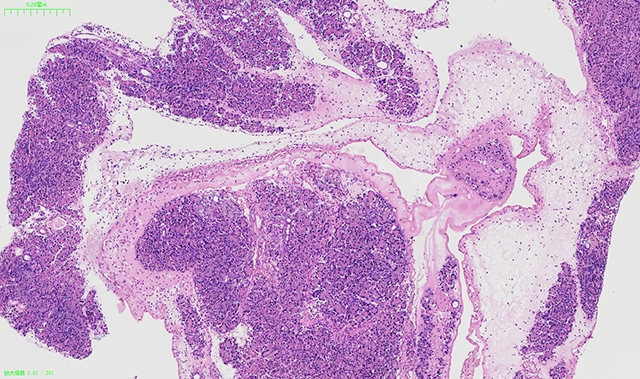

HE染色在诊断疾病方面起着至关重要的作用。通过观察染色后的组织样本,病理医生可以判断出病变的性质、范围以及与周围组织的关系。例如,在肿瘤的诊断中,HE染色可以帮助医生判断肿瘤的类型、分化程度以及是否侵犯周围组织……这些信息对于制定治疗方案和评估预后具有重要意义。